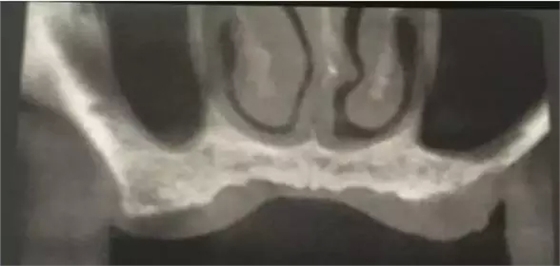

患者50歲,男性,身體健康。左上6,7缺失,骨高度2mm。

術前口內照和CT片。